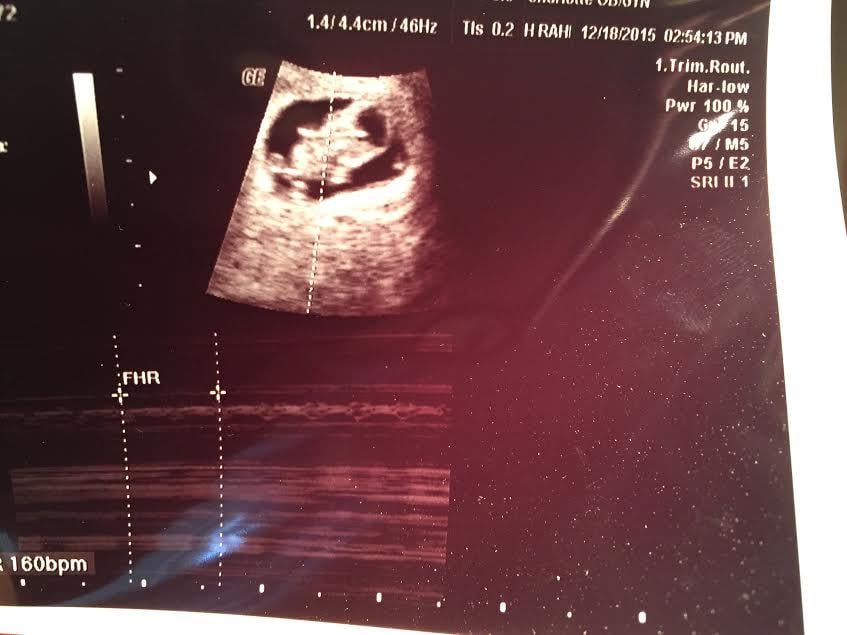

the u/s lady probably told me, but I was too busy just staring at the screen and tuning her out. I am curious as to what the ramzi theory would predict for me (I know it's not 100% accurate, but for fun)... anyone with any insight on my placenta location in this pic and the ramzi theory.. leave any comments! Thanks guys!

btw this is 8w5d